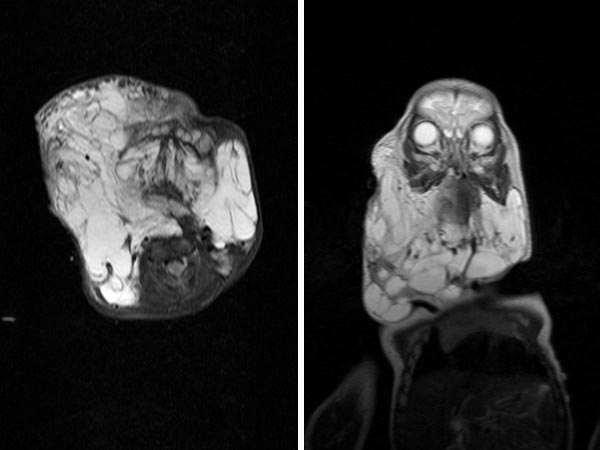

Der bisherige Behandlungsverlauf: 2012 bis 2013: 2 offen operative Resektionen im Weichteil submandibulär und erste Sklerosierungsbehandlung mit OK 432. In 2014: erneute offene Resektion von LM-Anteilen der Wange rechts über Facelift-Zugang mit Neuromonitoring des Nervus facialis, sublinguale Resektion, 2 x Sklerosierungsbehandlung mit OK 432. In 2015: CO2-Laserresektion von LM-Anteilen im Pharynx von enoral. In 2016: Verschluss des Tracheostomas, erneute Sklerosierungsbbehandlung mit OK 432. In 2017: 3 x Sklerosierungsbehandlung mit Bleomycin (10 mg, 15 mg, 15 mg), beim letzten mal kombiniert mit OK 432. In 2018: letzte offene Resektion submental und submandibulär rechts, damit jetzt Weichteilbehandlung vorerst abgeschlossen Das Bild zeigt das letzte MRT im Januar 2017.